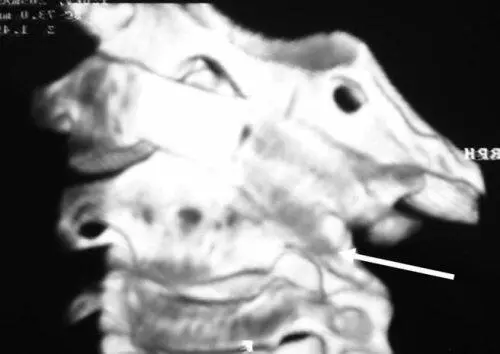

Накануне развития клиники кривошеи девочка делала кувырки. Жалоб не было. С утра почувствовала резкую боль в шее. Со слов девочки «голова отделялась от тела». По месту жительства в ЦРБ был поставлен диагноз миозит – лечилась тепловыми процедурами. Через 5 месяцев обратилась на неврологическое отделение ЦРБ в связи с сохранением клиники. Был поставлен диагноз синдром периферической цервикальной недостаточности, нестабильность CII–III. Получала физиотерапию, иммобилизацию воротником Шанца. Осмотрена ортопедом и заподозрен диагноз подвывих CI. Но тактика обследования и лечения не изменилась. Еще через 2 месяца переведена в центральную городскую больницу, где получала аналогичную помощь с диагнозом «корешковый синдром на фоне нестабильности шейного отдела позвоночника на уровне CII–CIII, позиционная правосторонняя кривошея». После 10 месяцев безуспешной терапии девочка переведена в неврологическую клинику педиатрической академии, где и была консультирована вертебрологом. Поставлен диагноз застарелый ротационный подвывих CI, который был подтвержден на КТ (рис. 6.11).

Рис. 6.11.3D КТ пациентки О., 5 лет. Выраженное косое положение атланта с захождением правого атланто-аксиального сустава (указано стрелкой)